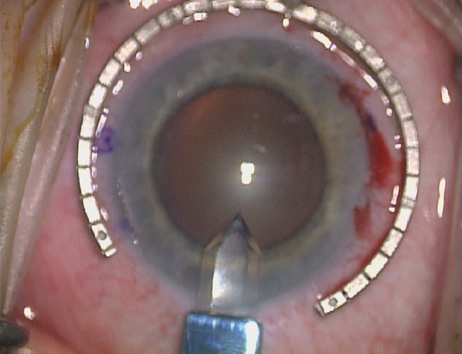

are, therefore, really intralimbal in nature. In creating the incision, it is important to hold the

knife perpendicular to the corneal surface in order to achieve consistent

depth and effect. Good hand and wrist support is important, and the

blade ought to be held as if one were throwing a dart such that the

instrument may be rotated between thumb and index finger as it is being

advanced, thus leading to smooth arcuate incisions. Typically, the

right hand is used to create incisions on the right side of the globe, and

the left hand for incisions on the left side. In most cases, it is

more efficient to pull the blade toward oneself, as opposed to pushing

it away. A lightly moistened corneal surface will help to prevent epithelial

As noted, in the setting of concomitant cataract surgery, an empiric blade

depth setting of 600 microns is commonly employed. Various knives

have been designed specifically for this application, ranging from disposable

steel blades to exquisite gemstone diamond knives. Synthetic (and

less expensive) diamond materials are also available and

are intended for limited reuse. Our preference is for diamond blade technology

that incorporates a single small and arced footplate for enhanced

visualization at the limbus (Mastel Precision). Two models

are available, one with a preset depth of 600 microns and the other

other manufacturers.   Fig. 6. (A)A diamond blade with a preset depth of 600 microns is used

to perform LRIs for routine cataract surgery. (B) An adjustable

depth micrometer blade is used in conjunction with the NAPA nomogram

when treating younger patients. Fig. 6. (A)A diamond blade with a preset depth of 600 microns is used

to perform LRIs for routine cataract surgery. (B) An adjustable

depth micrometer blade is used in conjunction with the NAPA nomogram

when treating younger patients.